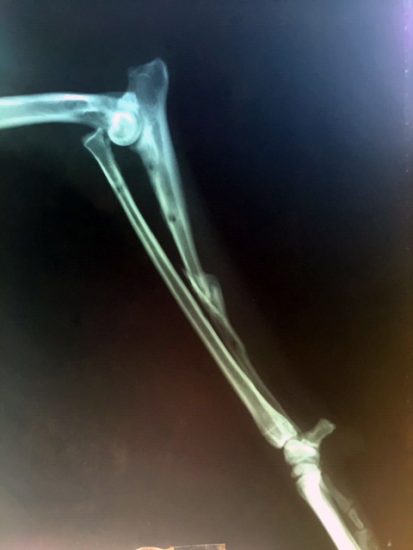

Bei so manchem würde man sich heute größere Transparenz wünschen, aber die X-Rays für Politischen Filz sind leider noch nicht erfunden worden. Bei Knochenbrüchen haben sie sich als sehr nützlich erwiesen. Hier ein Foto des zerbissenen Vorderbeins von Tito, meinem Hund.

Röntgen, der die Strahlung am 8. November 1895 zufällig entdeckte (eigentlich war er ganz anderen Phänomenen auf der Spur). schlug selbst den Namen X-Strahlen vor, und in den meisten Sprachen heißen sie weiterhin so (X-Ray, Rayon X, Raggi X). Auf Griechisch heißen sie richtigerweise ακτινογραφίες, also Strahlungszeichnungen.